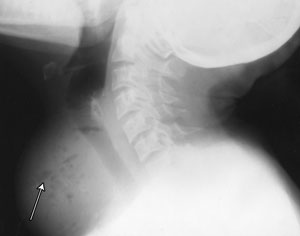

A 40-year-old woman presented with sudden onset of a painful neck swelling, fever and dysphagia. Examination revealed a warm, tender lump in her thyroid gland. Five weeks previously, she had had an abdominal hysterectomy with bilateral salpingo-oophorectomy for pelvic inflammatory disease. There was no evidence of leukopenia or diabetes. Computed tomography and x-ray images were consistent with a diagnosis of thyroid abscess (Figure 1 and Figure 2).